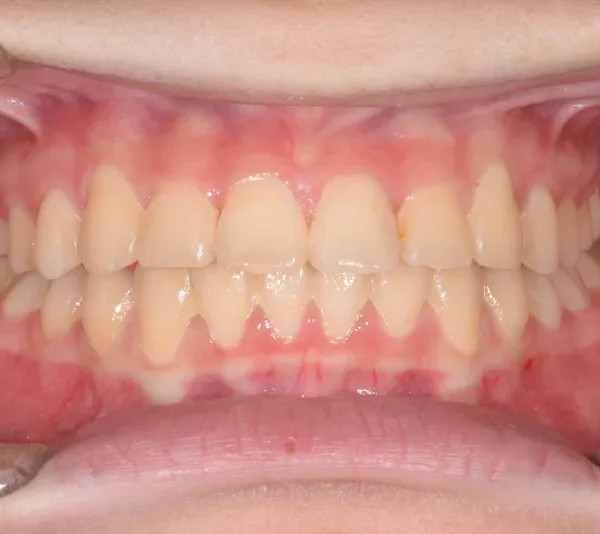

治療終了後